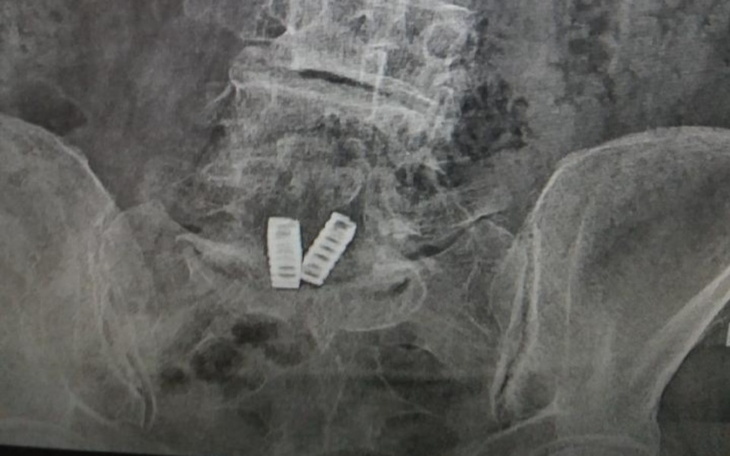

"Zwracam sie z prosba o pomoc i wsparcie finansowe . Jestem osoba bardzo schorowana z licznymi powaznymi schorzeniami . Nie chce obciążać Panstwa swoimi problemami , ale niestety nie mam innego wyjscia . Walcze o przetrwanie . W ostatnim czasie nastąpiło duze pogorszenie mojego stanu zdrowia , na tyle , ze mam problem z przejsciem nawet do toalety a nawet chwila w pozycji stojącej jest nie do zniesienia .Mam ogromne zmiany w kolanie i w kregoslupie . Lekarz zlecil endoproteze na ktora mnie nie stac . Zlecil jeszcze wstrzkniecie kolagenu probuje ratować staw kolanowy . Zlecil takze rezonans kolana i kregosłupa . Majac tak skromna emeryture nie stac mnie ani na leczenie ani na zakup lekow , ktore pochlaniaja cala moja emeryture . Dołączyła sie depresja . Brakuje na oplaty i zywnosc . Bardzo prosze o pomoc finansowa , jezeli moga Panstwo pomoc . Jest mi wstyd , ze bedac w tym wieku nie moge sobie poradzic , tak naprawde to nie widzę juz wyjscia z tej skompliko!